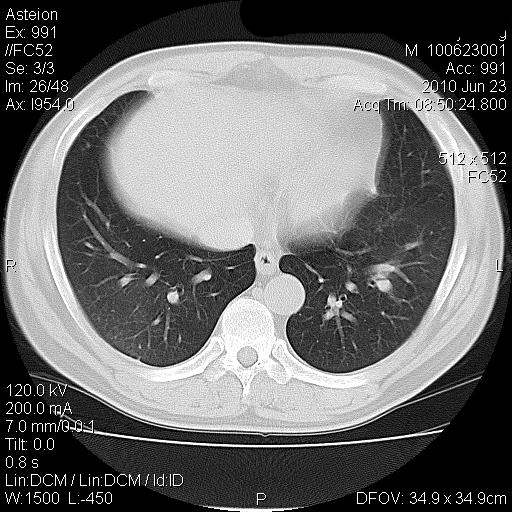

男 41岁 因发烧38-39度 这几天消炎治疗

化验结果 中性粒细胞比率升高(80.9) 淋巴细胞比率下降(10.2) 红细胞压积下降(33.4)

血小板平均分布密度升高(18.9)

双肺炎性灶【密度高 局限 考虑金葡菌 产血浆凝固酶所致】

病灶位于两上肺及右肺下叶背段,建议抗炎治疗后复查;结核不排外。

双肺炎性渗出病变,以右下肺为著。考虑金葡菌感染。

两肺多发结节斑块影,右下见支气管气相,支持两肺多灶性感染,抗炎治疗后复查。

双肺多发大小不等的团片状病灶,周围较模糊可见晕征,未见明显分叶征,纵膈淋巴结未见肿大。

考虑炎性病变。

双肺多发大小不等的团片状病灶可见于肺部炎性肉芽肿,也可见于肺淋巴瘤、肺淋巴瘤样肉芽肿、肺结核、肺部肿瘤,本例的影像表现结合临床考虑肺部炎性病灶。